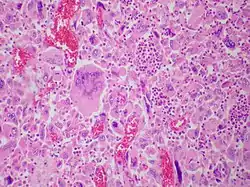

| Pulmonary giant cell carcinoma represents a rare variety of non-small cell lung carcinoma that is characterized by the presence of numerous tumor giant cells and an influx of inflammatory cells that are mostly polymorphonuclear leukocytes admixed with macrophages. The dense oval aggregates of polymorphonuclear leukocytes seen in this image are probably located in the cytoplasm of tumor giant cells (emperiopolesis) that have been sectioned in a plane that does not include their nuclei. | |

Both "tumor cell-tumor cell" and "leukocyte-tumor cell" emperipolesis (i.e. active penetration of the latter by the former) is very commonly seen in cases of GCCL.[12]